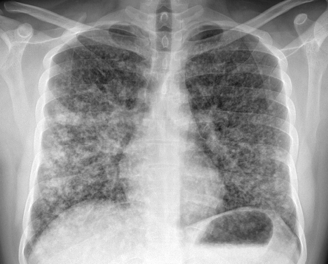

2) Imaging pearls—nodular pattern recognition

• Ask three things: craniocaudal distribution, symmetry, central vs peripheral.

• Centrilobular (spares pleura/fissures): airway-centered (e.g., NTM, bronchiolitis, tree-in-bud).

• Perilymphatic (tracks fissures/pleura & septa): sarcoid, lymphangitic spread.

• Random/diffuse (involves pleural surfaces): hematogenous spread → think miliary TB, disseminated fungal, septic emboli, metastatic disease.

• Interval change matters: new cavitation and confluence can upweight infection or aggressive malignancy.

• Young (26), subacute → chronic dyspnea/cough with diffuse pulmonary nodules; avoid premature closure on TB.